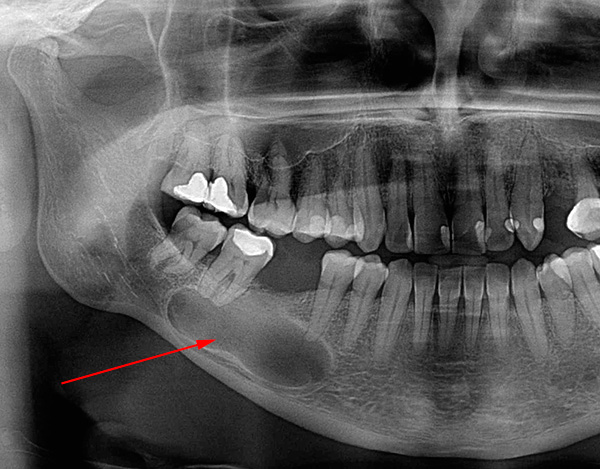

A foto abaixo mostra um exemplo de um cisto enorme, que não foi removido em tempo hábil e, tendo aumentado em volume, cresceu até as raízes de um dente adjacente:

É difícil determinar com uma imagem objetiva e mesmo com uma tomografia computadorizada com 100% de precisão que forma do processo inflamatório está presente na (s) raiz (s) do dente. Área de iluminação geralmente visível com contornos claros, geralmente arredondados ou ovais. Esse "círculo" pode ser localizado não apenas em uma raiz, mas também captura 2-3 raízes de um dente e até mesmo passa nas proximidades imediatas do topo das raízes dos dentes adjacentes, sugerindo ao dentista a escala da tragédia.